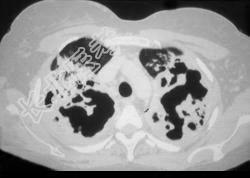

- 单项选择题一养鸽女,48岁, 发热,咳嗽, 咳脓痰带血半月余,请结合CT检查选出最可能的诊断 ( )

A、原发性肺结核

B、肺曲菌病

C、肺癌

D、间质性肺炎

E、支气管扩张